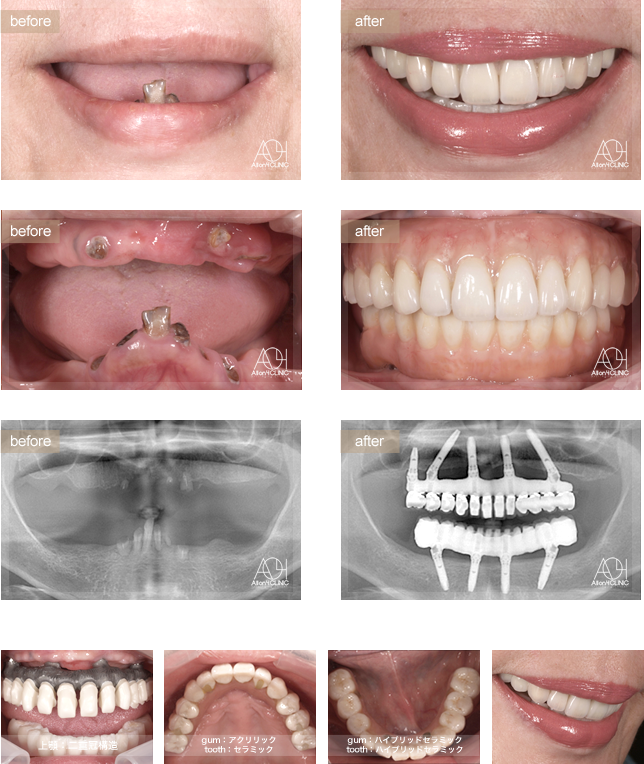

- Maxilla All-on-4

- Under All-on-4

上顎は5本のインプラントを埋入。下顎はAll-on-4。

上顎上部構造は二重冠構造(歯肉:アクリリックレジン歯:セラミック)を採用。

下顎はハイブリッドタイプ(歯肉:ハイブリッドセラミック歯:ハイブリッドセラミック)。 上下顎チタンPIBフレーム。